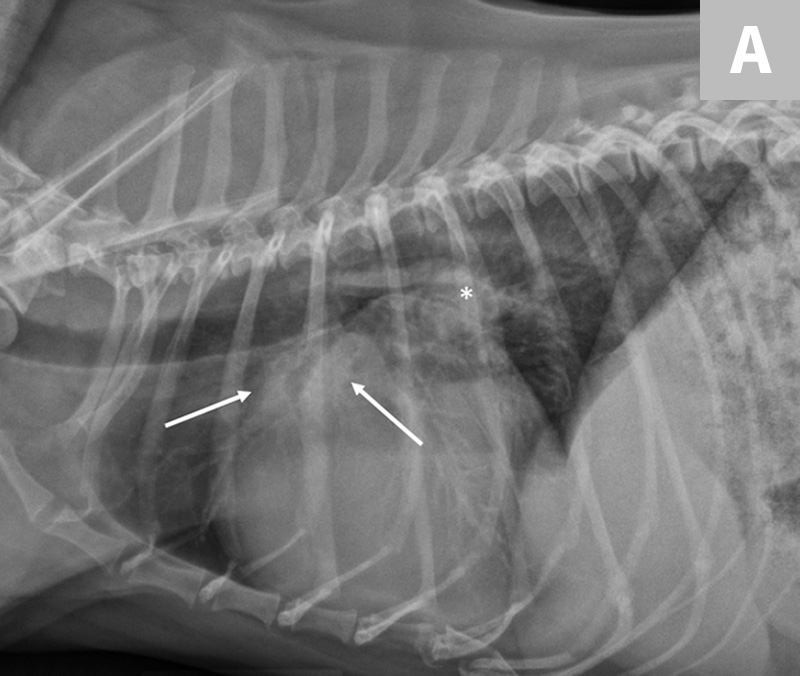

Congestive Heart Failure Symptoms In Dogs

Left Sided Congestive Heart Failure Clinician s Brief

Understanding The Risk Of Congestive Heart Failures In Dogs Bark For More